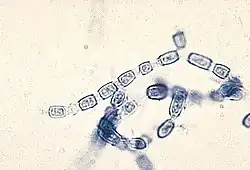

C. immitis can cause a disease called coccidioidomycosis (valley fever).[8][9][10] Its incubation period varies from 7 to 21 days.[11] Coccidioidomycosis is not easily diagnosed on the basis of vital signs and symptoms, which are usually vague and nonspecific. Even a chest X-ray or CT scan cannot reliably distinguish it from other lung diseases, including lung cancer. Blood or urine tests are administered, which aim to discover Coccidioides antigens. However, because the Coccidioides creates a mass that can mimic a lung tumor, the correct diagnosis may require a tissue sample (biopsy). A Gomori methenamine silver stain can then confirm the presence of the Coccidioides organism's characteristic spherules within the tissue. The C. immitis fungus can be cultured from a patient sample, but the culture can take weeks to grow and requires special precautions on a part of the laboratory staff while handling it (screw cap vials and sterile transfer hoods are recommended).[12] It is reported as the tenth-most often acquired infection in the laboratory conditions with two documented deaths.[2] Until October 2012, C. immitis had been listed as a select agent by both the U.S. Department of Health and Human Services and the U.S. Department of Agriculture, and was considered a biosafety level 3 pathogen.